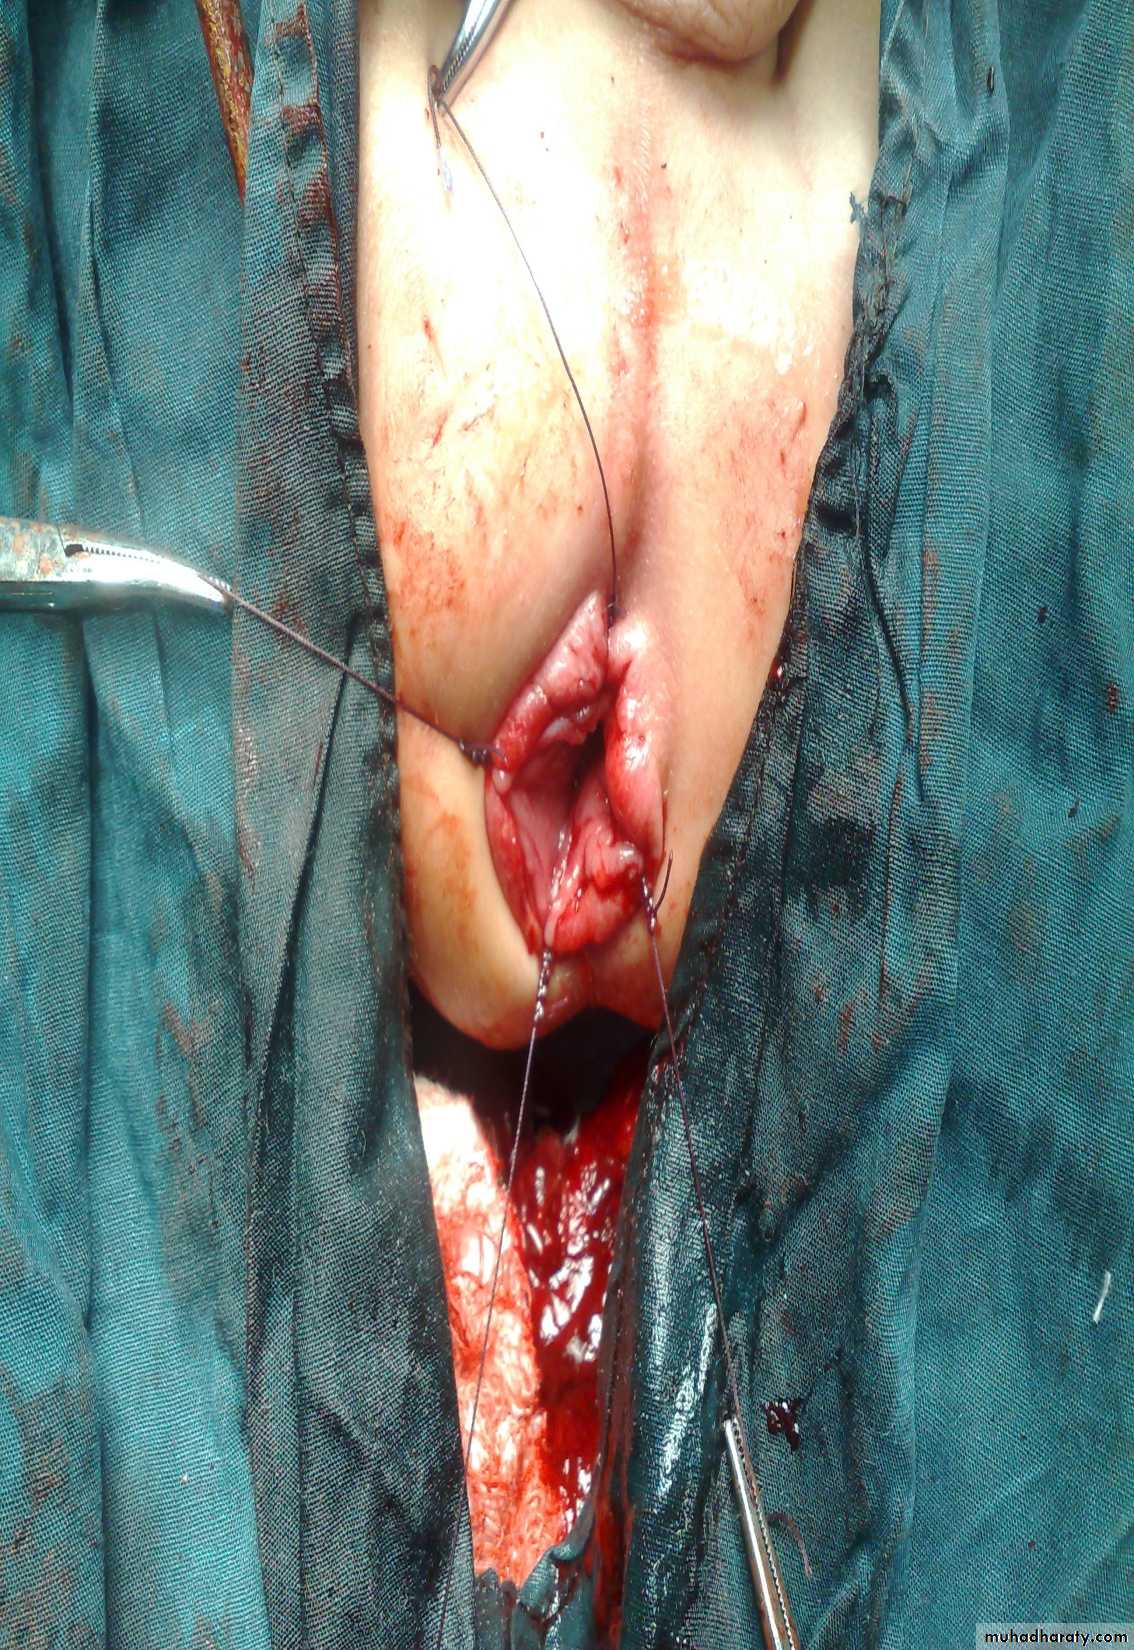

Anorectal Anomalies

First and second photos:

Lateral invertogrampubococcygeal line

It is low type

Third photo:

Supine type of view

Low type

Anal dimplePass of meconium through the urethra

High typeSubcutaneous meconium – cutaneous fistula – low type